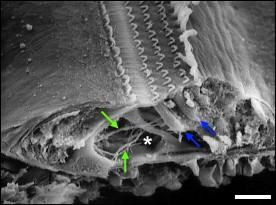

Imagerie médicale montrant les 3 rangées de CCE et l´unique rangée de CCI. à la base de ces dernières le nerf auditif commence.

Schéma du principe d´excitation des céllules cilliées et de leurs petits cils (stéréocils) - l éxcitation déclenche un phénomène chimique.